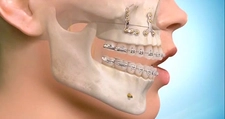

Dogo Çenesinin Gücü Ne Kadar Ton Basabiliyor?Dogo Argentino, güçlü yapısıyla dikkat çeken bir köpek ırkıdır. Bu ırk, av köpeği olarak yetiştirilmiş olup, kaslı yapısı ve güçlü çenesi ile bilinir. Dogo Argentino'nun çene gücü, hem avcılık yetenekleri hem de koruma işlevleri açısından oldukça önemlidir. Bu makalede, Dogo'nun çene gücünü detaylı bir şekilde inceleyeceğiz. Dogo Argentino'nun Çene AnatomisiDogo Argentino, güçlü bir çene yapısına sahip olmasıyla birlikte, bu güçlü yapı birkaç anatomik özellikten kaynaklanmaktadır:

Çene Gücü ve Basınç ÖlçümüBir köpeğin çene gücünü ölçmek için genellikle "bite force" (ısırma gücü) terimi kullanılır. Dogo Argentino'nun çene gücü, 450 psi (pound per square inch) civarında ölçülmüştür. Bu, Dogo'nun çenesinin yaklaşık 20-30 ton basma kapasitesine sahip olduğu anlamına gelir. Bu güç, Dogo'nun avını yakalama ve tutma yeteneğini büyük ölçüde artırır. Çene Gücünün ÖnemiDogo Argentino'nun çene gücü, birkaç açıdan önem taşımaktadır: